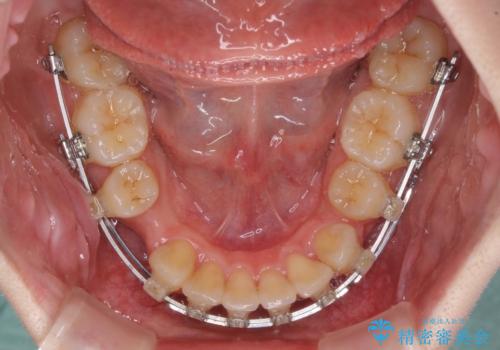

- クリアブラケット

- 3年10ヶ月

- 下顎の前歯が上顎の歯肉に咬みこむくらいに突出した上顎前歯を気にして来院された患者様です。

口元の突出感はないものの、上顎前歯が前方に傾斜して突出しており、前後に大きなズレがあり非常に深い咬み合わせとなっていました。

前突間を改善するため、上顎左右の第一小臼歯を抜歯してワイヤー装置にて矯正治療を行うこととしました。

深い咬み合わせは上顎前歯を引っ込ませる大きな障害となるため、咬み合わせの改善が非常に重要となります。やや期間はかかりましたが、当初狙った通りの仕上がりで治療を終えることができました。